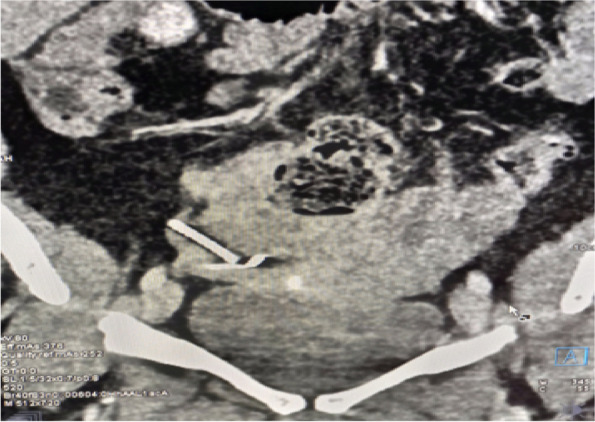

Background: Loss of Intra Uterine Device (IUD) following silent perforation of the uterus either during or after IUD insertion is an uncommon finding due to a lack of immediate follow-up. We report a rare case in which uterine perforation following the migration of IUD to the right fallopian tube without visceral injury. The patient presented with lower abdominal pain and pain during sex for one year since IUD insertion. On examination, we noted tenderness on the right suprapubic region and on speculum examination, no IUD thread was seen. A radiological pelvic examination showed an empty uterus without an IUD. Laparotomy and retrieval of migrated IUD was done followed by repair of perforated uterus.

Abstract Image